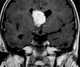

Giant cell astrocytoma

Subependymal giant cell astrocytoma (SEGA, SGCA, or SGCT) is a low-grade astrocytic brain tumor (astrocytoma) that arises within the ventricles of the brain. It is most commonly associated with tuberous sclerosis complex (TSC). [Source: Wikipedia ]